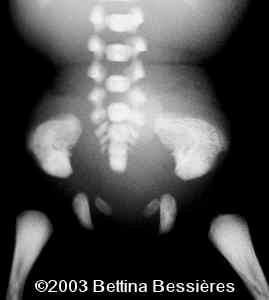

Abnormal vertebrae.

case0093-17

The radiohumeral fusion, and abnormal vertebrae:

case0093-08

case0093-09